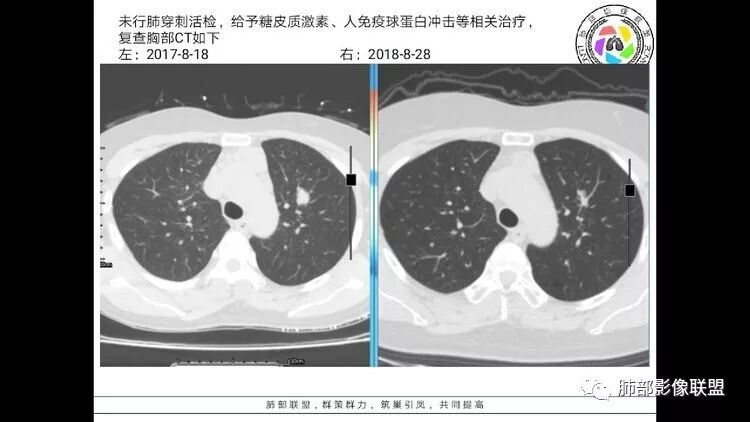

老年女性,眼炎入院,血常规正常,双肺多发囊状影,病变随机分布,形态单一,与血管关系密切,考虑LIP。左下肺混合GGO,边界尚清,贴近囊腔,鉴别腺癌。炎症指标无异常暂不考虑感染性病变。

患者中年女性,以眼部症状就诊。

胸CT:1.双肺多发囊性变,以中下肺为主,病变边缘可见肺动脉,部分囊内可见分隔及肺动脉,双下部分肺野周围可见小叶中心结节及树丫征。

2 左肺上叶尖后段 右肺上叶前段 右肺下叶外基底段 结节影,边界清楚,可见柔软毛刺,左肺下叶后基底段混合密度影。

3.纵隔淋巴结肿大?,以主动脉弓为界向上向下增大。

考虑:淋巴瘤肺浸润,眼部症状考虑与此有关;LIP?;继续鉴别肺腺癌?血管炎?。

患者中年女性,因右眼红痛1天就诊。胸CT:双肺多发囊性变及结节影,囊以中下肺为多,部分囊内可见分隔及肺动脉,结节部分为实性,部分为混合性,边缘光滑,未见明显毛刺、棘突、胸膜牵拉及血管集束征象。双中下可见支气管扩张及树丫征。淋巴结无明显肿大。综合考虑:一元淋巴细胞间质性肺炎。多元鉴别肺腺癌并转移等恶性病变。

结果

总结

LIP影像重要线索一句话:

双肺下叶分布为主的间质改变(磨玻璃影、小叶间隔增厚)、散在气囊影(常有血管贴边)、边界不清小结节